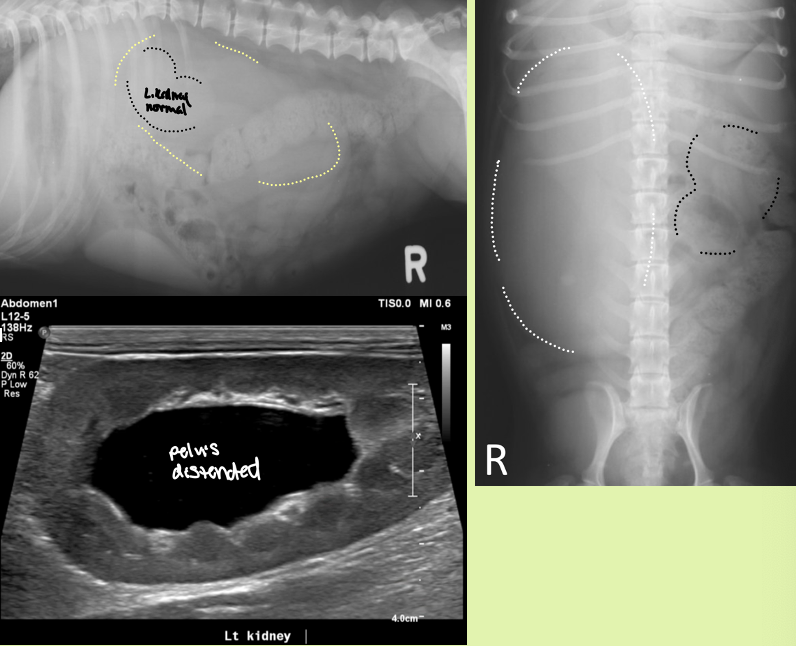

hydronephrosis is caused by

partial or complete obstruction of urine outflow in renal collecting system or ureters

4 causes of congenital vs acquired hydronephrosis

Congenital

kinking or partial obstruction of ureters 2° to kidney or ureteral malposition

Stenosis

compression from ureterocele

associated with ectopic ureters or other congenital malformations without true obstruction

Acquired

Obstruction from urinary calculi, neoplastic or inflam masses

accidental ligation

ureteral stricture

parasites (dioctophyma renale)

enlarged smooth kidneys with distended pelvis ± distended ureters

hydronephrosis